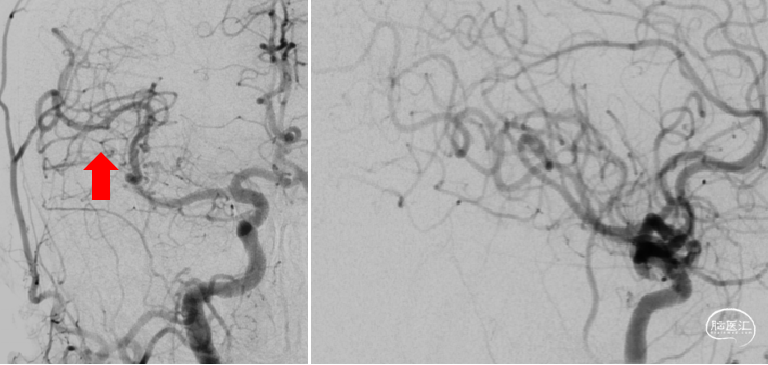

以8F导引导管做支撑送入右侧颈内C1段,同轴送入132cm-AXS Catalyst-6中间导管、150cm-0.021-Trevo Pro 18微导管、200cm-0.014-Synchro2微导丝;CAT-6送至M1段闭塞处;微导管送入右侧大脑中动脉M2段后,1ml注射器回抽见血液回流再手动造影。

选用4mm×20mm-Trevo Provue取栓支架,将有效段远端放置于大脑后动脉开口处,后退微导管释放支架,见支架尾端存在可疑的释放不全感,提示可能的血栓/狭窄。静待5分钟使支架与血栓镶嵌更紧密。

仅将支架末端无效段拉至CAT-6里面,CAT-6的Y阀处连接50ml注射器负压持续抽吸,同时将中间导管及支架拉出体外,见一35mm×2mm长条血栓附着于支架上,随后20ml注射器于长鞘内再次抽吸,可见顺畅血流进入注射器。

复查造影:下干完全再通。

3. 再看手术策略,溶栓后大脑中动脉M1段再通,可疑血栓前移致M2段闭塞。术中采用支架联合取栓SWIM技术,一是防止抽吸时血栓远端拉断而造成逃逸,二是通过支架嵌入包裹血栓有助于弯角处血栓的取出。术者在术前把手术中可能会遇到的各种障碍都考虑的非常到位,针对性的制订了手术方案,这种未雨绸缪的手术思路将大大提高手术的顺畅度和成功率。术者在支架释放后,观察到支架尾端存在展开不完全的情况,抽拉时仅将支架末端无效段拉至CAT-6里面,CAT-6连接负压持续抽吸,同时将中间导管及支架拉出体外。防止了支架上的嵌入的栓子被中间导管口的剥脱而逃逸,从取出的血栓是挂在支架的远段位置可以看出,这一细节操作的必要性。

手术开始时,造影发现M2段闭塞,此时可考虑使用管腔更小的CAT-5 132mm,或许可以实现直接接触血栓,ADAPT抽吸成功。